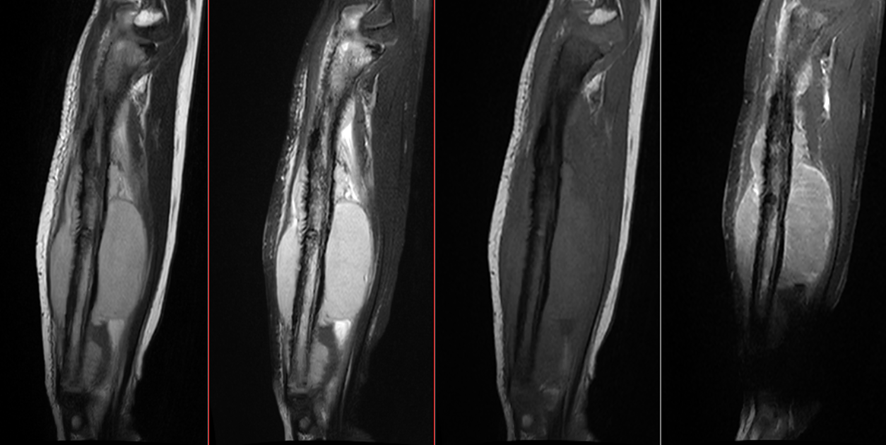

骨肉腫とユーイング肉腫の診断には、通常、X 線、 CT スキャン、 MRI スキャンなどの画像検査と、罹患した骨または組織の生検を組み合わせて行われます。血液検査は、特定の腫瘍マーカーを特定することにより診断にも役立ちます。

医療専門家は、MRI スキャンを使用して骨髄および追加の軟組織を詳細に観察することがあり、これは腫瘍の範囲を特定し、他の領域に転移しているかどうかを判断するのに役立ちます。

CT スキャンは、さらなる評価に役立つ場合があります。ただし、医療専門家は通常、MRI を受けられない人に対してのみこの検査を指示します。